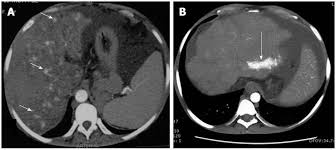

Chiasmata -mə-tə or chiasmas also chiasms 1. Esophageal varices are extremely dilated sub-mucosal veins in the lower third of the esophagus. Located in metro Denver northern Colorado and western Nebraska serving all of the Front Range our team consists of board-certified and fellowship-trained interventional radiologists. This results in hepatic congestion similar to Budd-Chiari syndrome and post-sinusoidal portal hypertension. The patients condition should be monitored throughout the procedure. They are most often a consequence of portal hypertension commonly due to cirrhosis. Toxic injury to liver sinusoids causes sloughing of endothelial cells that embolize to hepatic venules and cause eventual fibrosis of the venules. Coin in the Esophagus. There is no clear consensus regarding the number of occluded veins some authors claim that there should be at least one occluded hepatic vein 7 others state that there are no significant.

Carcinoma of the Colon. Budd-Chiari syndrome a blockage in one or more veins that carry blood from the liver back to the heart. And coumarin skin necrosis adrenal gland hemorrhage and infarction. Toxic injury to liver sinusoids causes sloughing of endothelial cells that embolize to hepatic venules and cause eventual fibrosis of the venules. Chiari malformation CM is a structural defect in the cerebellum characterized by a downward displacement of one or both cerebellar tonsils through the foramen magnum the opening at the base of the skull. Embolism and thrombosis of. La présence dune ou plusieurs affections prothrombotiques est fréquente La prise en charge repose sur un traitement anticoagulant précoce le traitement de l.